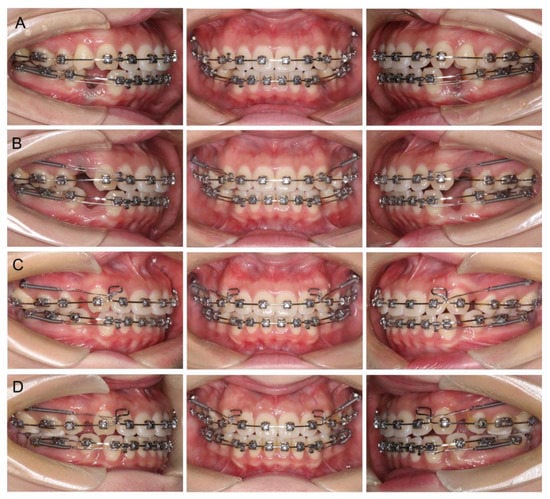

2.4. Treatment Progress